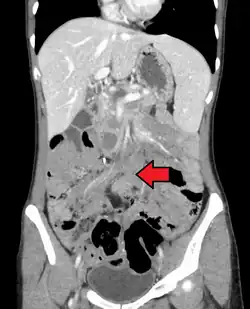

![]() Guz desmoidalny w jamie brzusznej, rezonans magnetyczny | |

Podejrzenie guza desmoidalnego jest stawiane na podstawie badań obrazowych, z których największe znaczenie kliniczne ma rezonans magnetyczny. Ostateczne rozpoznanie wymaga pobrania biopsji guza i oceny histopatologicznej[4].

Badania obrazowe pełnią istotną rolę w diagnostyce guza desmoidalnego. Pozwalają na rozpoznanie guza położonego w obrębie tkanek miękkich oraz ustalenia jego dokładnej lokalizacji, marginesów oraz stosunku do ważnych struktur anatomicznych. Pozwala to na zaplanowanie dalszej diagnostyki oraz określenie możliwości wykonania zabiegu operacyjnego[50]. Ponadto metody diagnostyki obrazowej znajdują zastosowanie w monitorowaniu progresji choroby podczas obserwacji oraz odpowiedzi na leczenie ogólnoustrojowe[5].

- Tomografia komputerowa

Tomografia komputerowa (TK) jest przydatnym narzędziem w diagnostyce guza desmoidalnego. Pozwala rozpoznać obecność litego guza w obrębie tkanek miękkich, określić jego lokalizację i rozmiar[5]. Jest pomocną metodą w diagnostyce powikłań guza związanych z jego lokalizacją[50]. W tomografii komputerowej guz desmoidalny jest słabo widoczny, ponieważ guz jest izodensyjny lub lekko hipodensyjny względem mięśni. Zmiana ze względu na bogate unaczynienie naczyń włosowatych ulega wzmocnieniu kontrastowemu[50][51]. Ze względu na inwazyjny wzór wzrostu marginesy zmiany mogą być słabo odgraniczone[50].